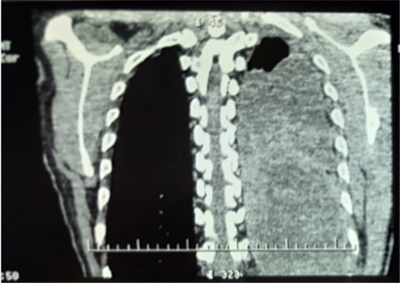

患者劉某,男性,52歲。因“胸悶、胸痛1月,發(fā)熱10余天”,就診于當(dāng)?shù)乜h醫(yī)院CT提示左側(cè)胸腔大量積液,予胸腔閉式引流同時(shí)抗感染治療,效果不佳遂轉(zhuǎn)入我院胸外科。復(fù)查胸部CT提示胸腔腫瘤合并胸腔積液。

入院后經(jīng)胸外科全體醫(yī)師對患者病情進(jìn)行綜合分析、積極術(shù)前準(zhǔn)備,于2月21日為患者實(shí)施手術(shù)治療。術(shù)中發(fā)現(xiàn)患者左側(cè)胸腔巨大腫瘤占位,體積約一個(gè)西瓜大小,幾乎完全占據(jù)了整個(gè)左側(cè)胸腔,左肺大部分被壓縮而失去功能,腫瘤與周圍組織粘連致密。切開腫物,其內(nèi)見大量魚肉樣物質(zhì)及黃色纖維素樣物質(zhì),取部分內(nèi)容物及腫物囊壁送檢冰凍切片,回示淋巴樣異型細(xì)胞。繼續(xù)游離,清除腫物內(nèi)容物,并予切除部分囊壁。

通過6小時(shí)的努力將腫瘤完全切除,出血約2000ml。術(shù)后病理檢查最終確診為胸腔尤文氏肉瘤。此種胸腔巨大腫瘤,手術(shù)難度大,術(shù)中出血多,手術(shù)風(fēng)險(xiǎn)高。